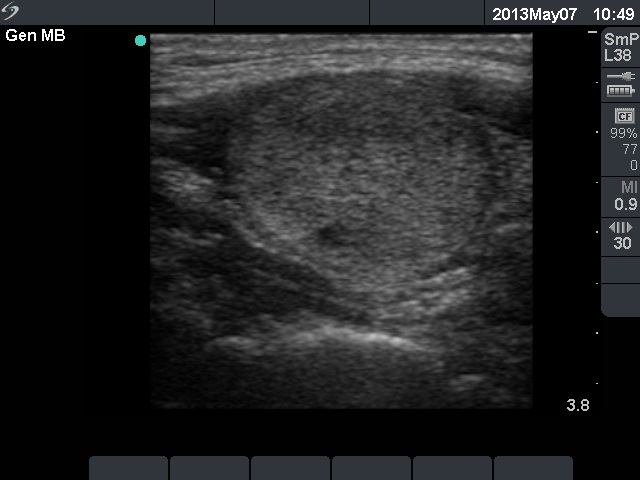

Ethanol sclerotherapy: non-toxic solid nodules - Case 5

Ten years after the therapy (ultrasonographic picture 5)

Left lobe, longitudinal scan.